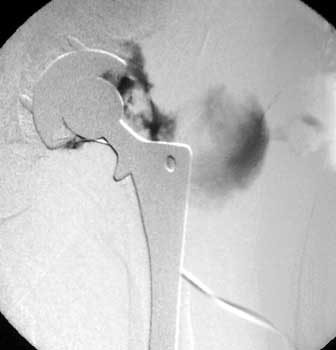

Dry tap secondary to sinus tract decompression

Sinus tract draining posteriorly